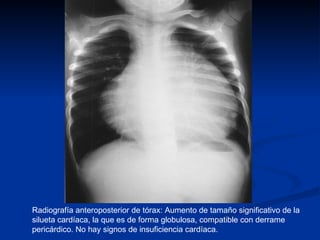

Radiografía anteroposterior de tórax: Aumento de tamaño significativo de la silueta cardíaca, la que es de forma globulosa, compatible con derrame pericárdico. No hay signos de insuficiencia cardíaca.

Radiografía anteroposterior detórax: Aumento de tamaño significativo de la silueta cardíaca, la que es de forma globulosa, compatible con derrame pericárdico. No hay signos de insuficiencia cardíaca.